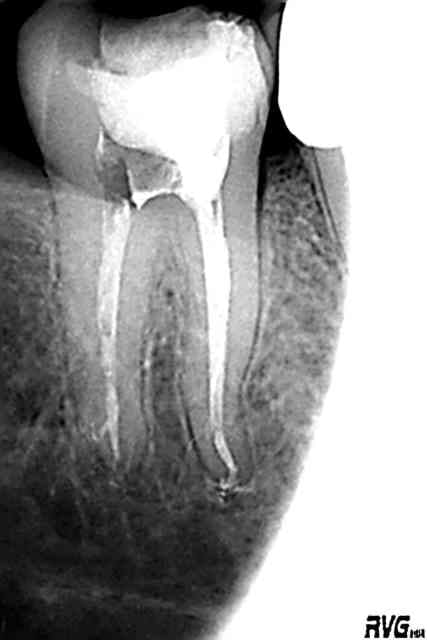

et pour le plaisir des yeux, quelques cas qu'il m'a envoyé...

etonnante tout de meme cette 21 et son canal lateral, visiblement il le voulait celui la (ou est ce une image de resorption intra?), s'il l'a vu avant je me demande bien comment il a fait...

y a bien une résorption interne. pj la préop